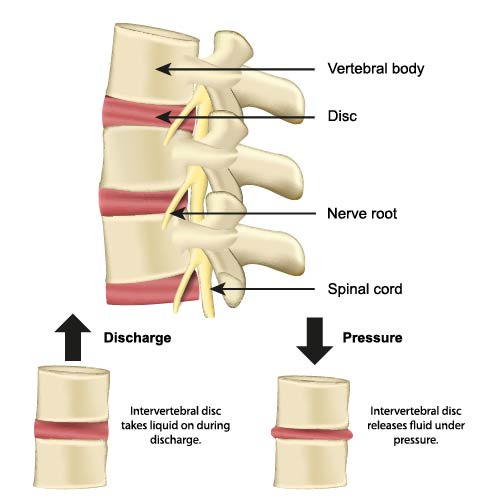

The illustration offers a simplified view of the vertebral column, emphasizing the intervertebral discs and their role in accommodating pressure changes. It offers a side view of the spine, where we can see several vertebral bodies stacked on top of each other with intervertebral discs between them, as well as the spinal cord and emerging nerve roots.

The intervertebral discs are key structures in the spine that serve as cushions between the individual vertebrae. The diagram illustrates two conditions of these discs: when they take in liquid during ‘discharge’ and when they release fluid under ‘pressure’. This dynamic process allows the discs to absorb shocks and maintain flexibility in the spinal column.

Under ‘discharge’, when the spine is unloaded or in a state of relaxation, the intervertebral discs can imbibe or take in water, which helps to maintain their height and elasticity. Conversely, under ‘pressure’, such as during standing, walking, or lifting, the discs release water. This mechanism is crucial for the discs’ ability to handle mechanical stress.

Additionally, the diagram shows the spinal cord running through the vertebral canal and the nerve roots branching out from it. The health and function of intervertebral discs are important not only for spinal mobility but also for the protection of these nerve structures.

Understanding the biomechanics of the intervertebral discs is important for recognizing how activities and posture can impact spinal health and for understanding the mechanisms behind conditions such as disc herniation, where a disc’s nucleus pushes out through a tear in the annulus fibrosus, potentially compressing a nerve root and causing pain.